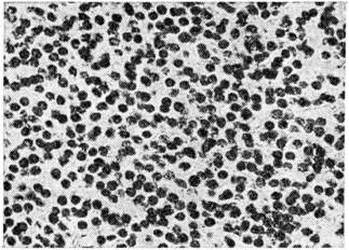

Микроскопически различают Олигодендроглиома типической и атипической структуры. Типические Олигодендроглиома состоят из густо и равномерно расположенных клеток со скудной цитоплазмой и ядрами сферической формы с нежными глыбками хроматина и чётким ядрышком (рисунок 2), напоминающих обычный олигодендроглиоцит. Нередко ткань опухоли приобретает мелкоячеистую (напоминающую соты) структуру, в центре ячейки располагается по нескольку ядер, окружённых светлой неокрашенной зоной (рисунок 3). Иногда в ткани Олигодендроглиома наряду с клетками, напоминающими олигодендроглиоциты, обнаруживают пучки веретенообразных клеток с отростками и ядрами вытянутой формы. В ряде случаев в Олигодендроглиома встречаются участки астроцитомы (смотри полный свод знаний), которая содержит глиальные волокна, импрегнирующиеся методом Рамон-и-Кахаля. Подобные опухоли диагностируются как олигодендроастроцитомы.. В Олигодендроглиома имеется небольшое или умеренное количество мелких сосудов. Характерным является отложение солей извести в ткани опухоли, сосудах и прилежащем мозговом веществе. Нередки мелкие кисты.

Рис. 2.

Микропрепарат олигодендроглиомы типической структуры: все поле зрения покрыто округлой формы опухолевыми клетками со скудной цитоплазмой; окраска гематоксилин-эозином; × 400.